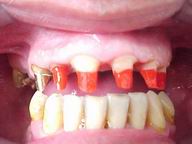

Reabilitação funcional e estética em ambas as arcadas

com próteses fixas e removíveis de encaixe de precisão.

ANTES